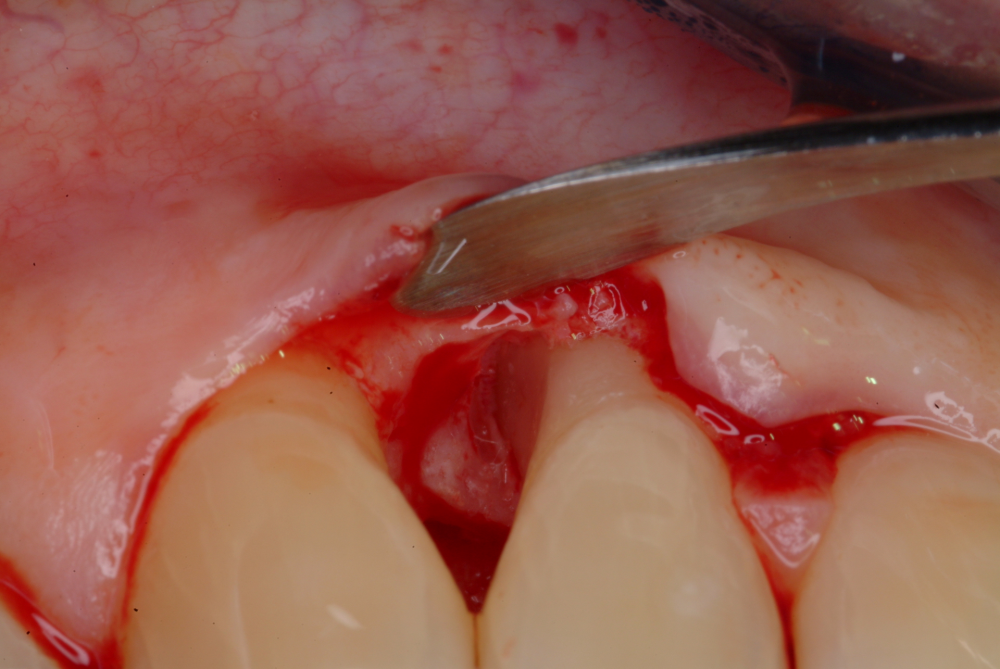

The Advanced Training Workshop on Soft Tissue Management and Treatment of Peri-implantitis is an interactive course aiming at clinicians wishing to upgrade their skills in the soft tissue management around implants to treat mucogingival deficiencies and in the application of non-surgical and surgical treatment to peri-implant diseases. The course consists of an integrated approach designed to build and extend the competence of the practicing periodontist in the area of contemporary mucogingival surgery, peri-implant surgery, microsurgery and minimally invasive surgery. The topics will be covered with lectures powered by 2D and 3D video demonstrations, case discussions, and focused hands-on training on animal and silicon models.